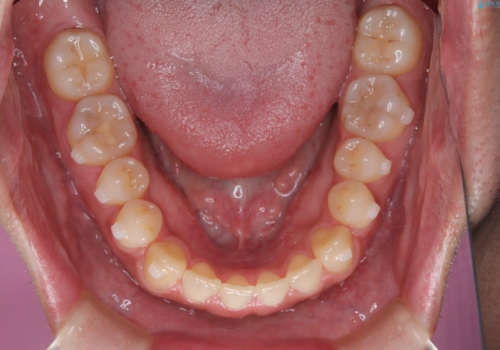

- 前歯がすきっ歯であることを気にされて来院された患者様です。上下顎のアーチを整える治療計画を立案し、マウスピースにて治療しました。とてもまじめに使用していただき、気になっていた隙間も順調に閉鎖しました。